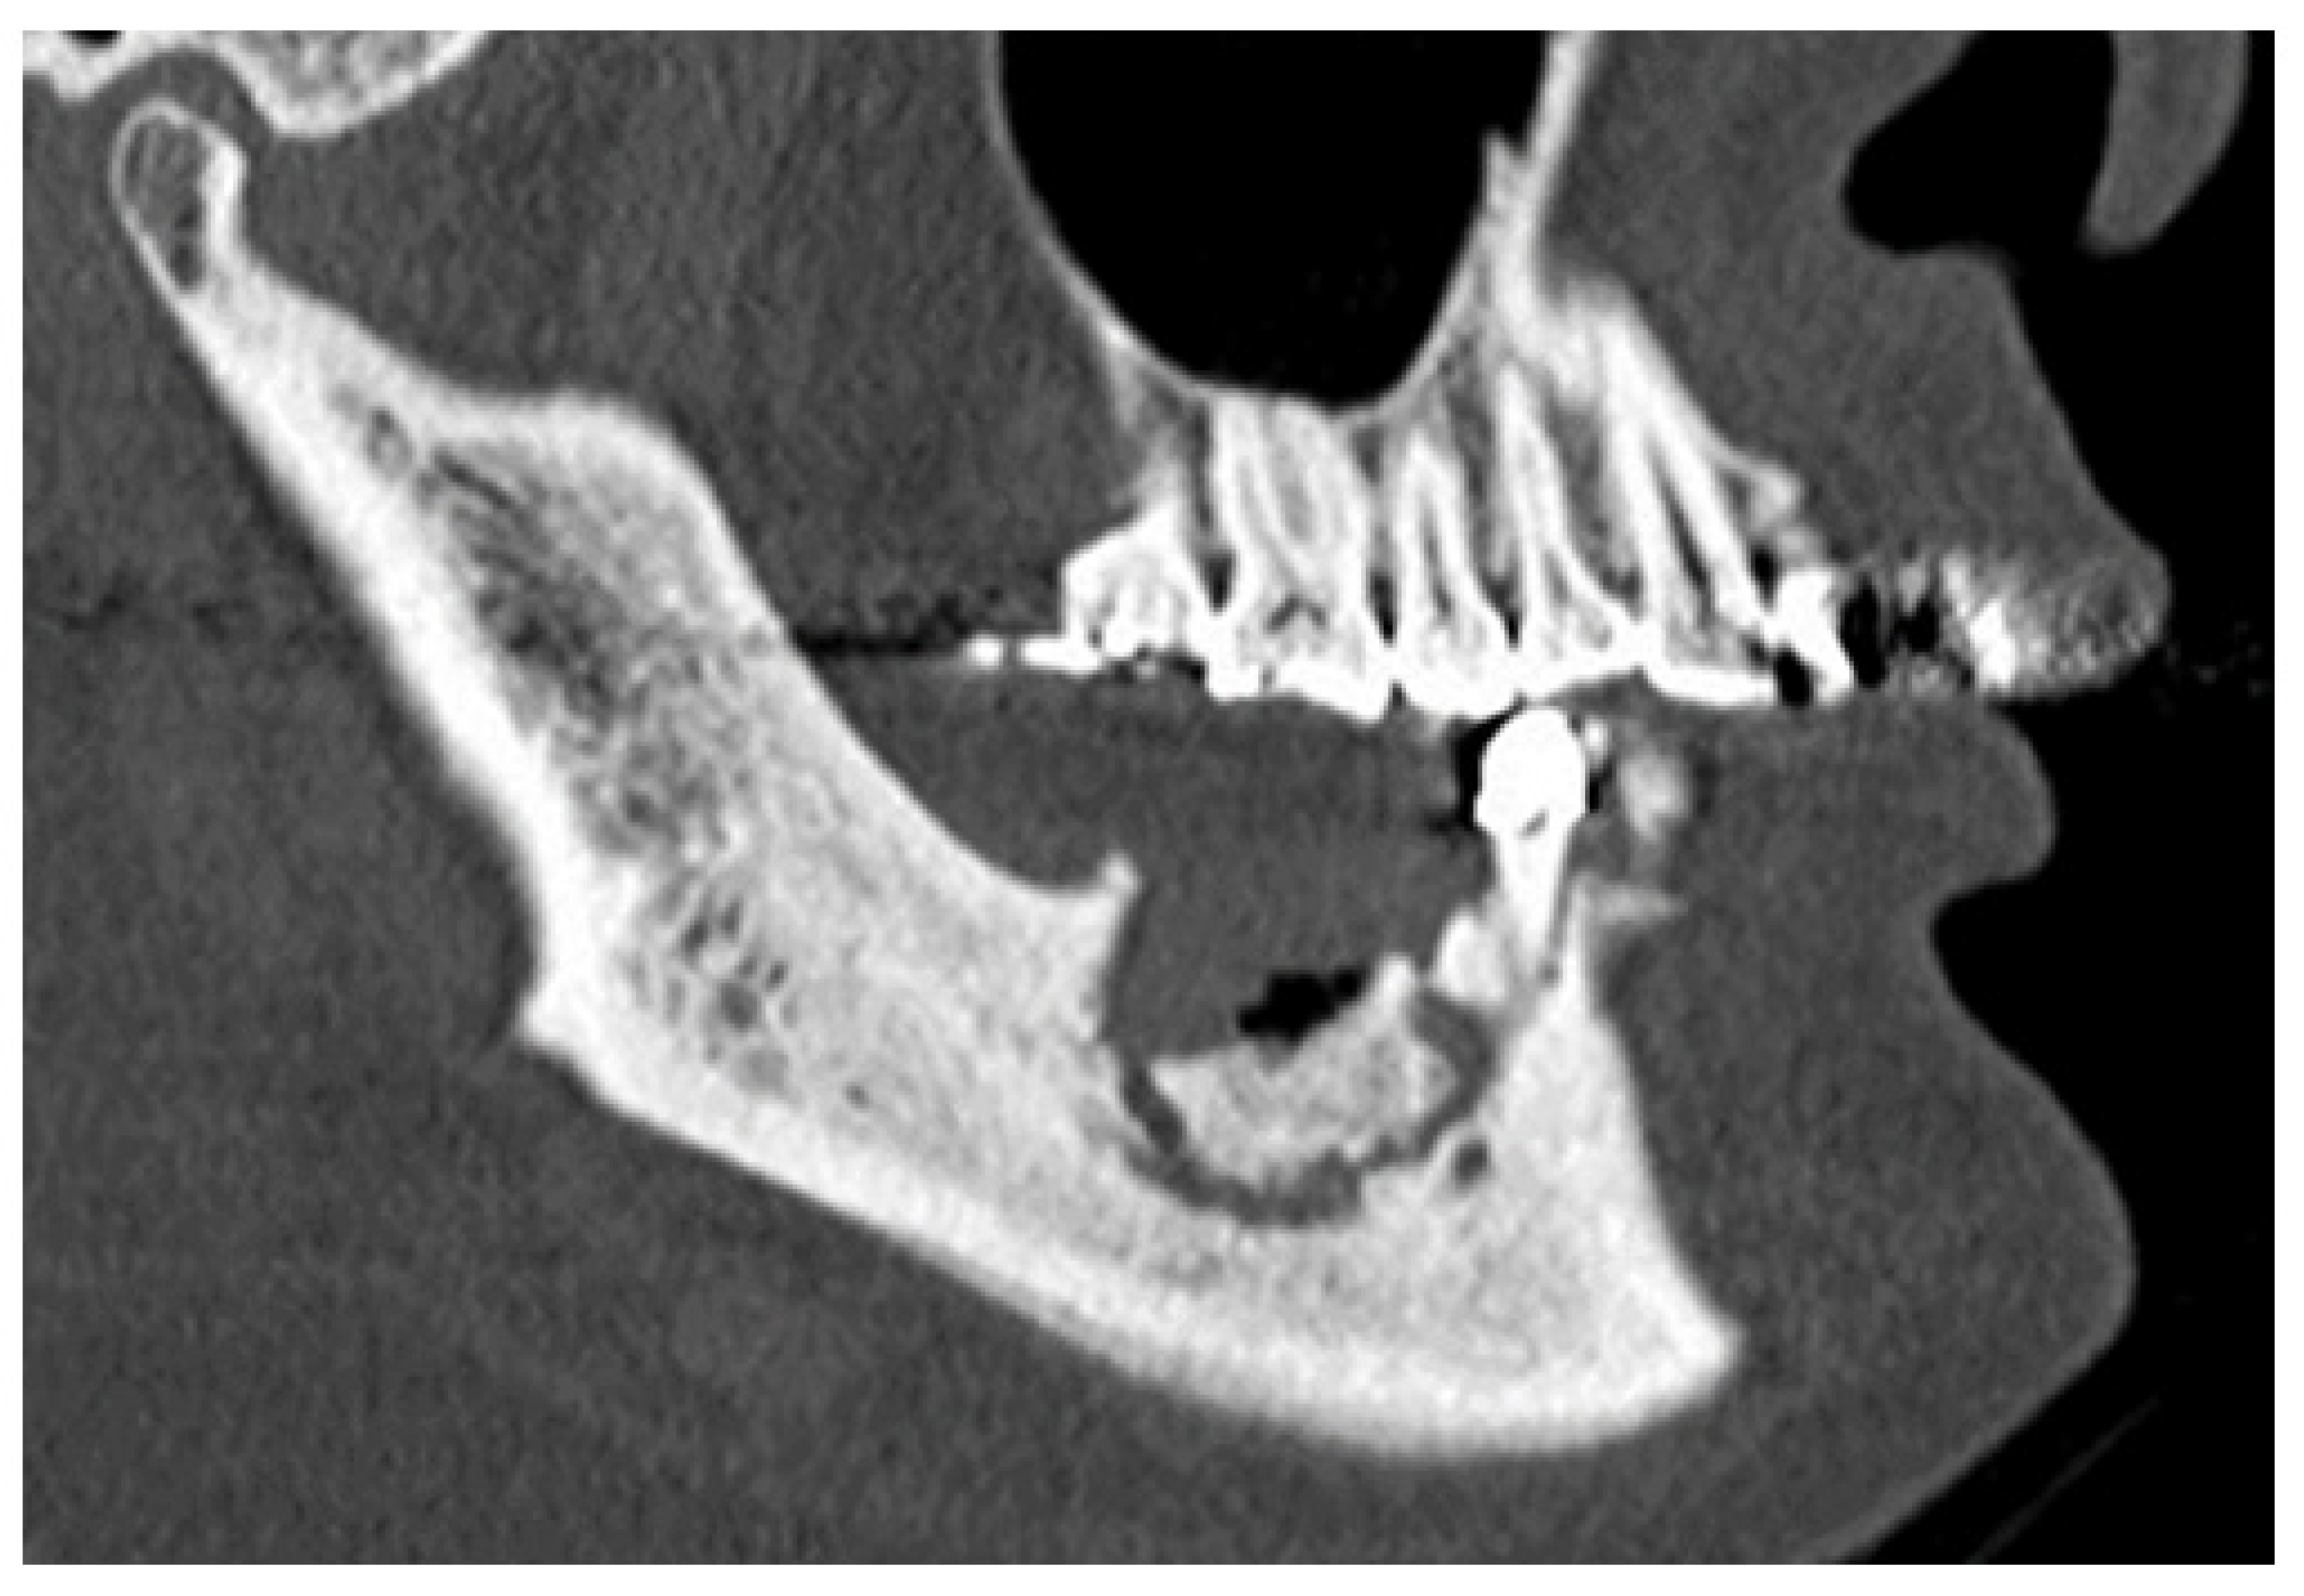

| Extent of osteolytic area | localized | 75 |

| extended | 28 | |

| Periosteal reaction | (−) | 75 |

| (+) | 28 | |